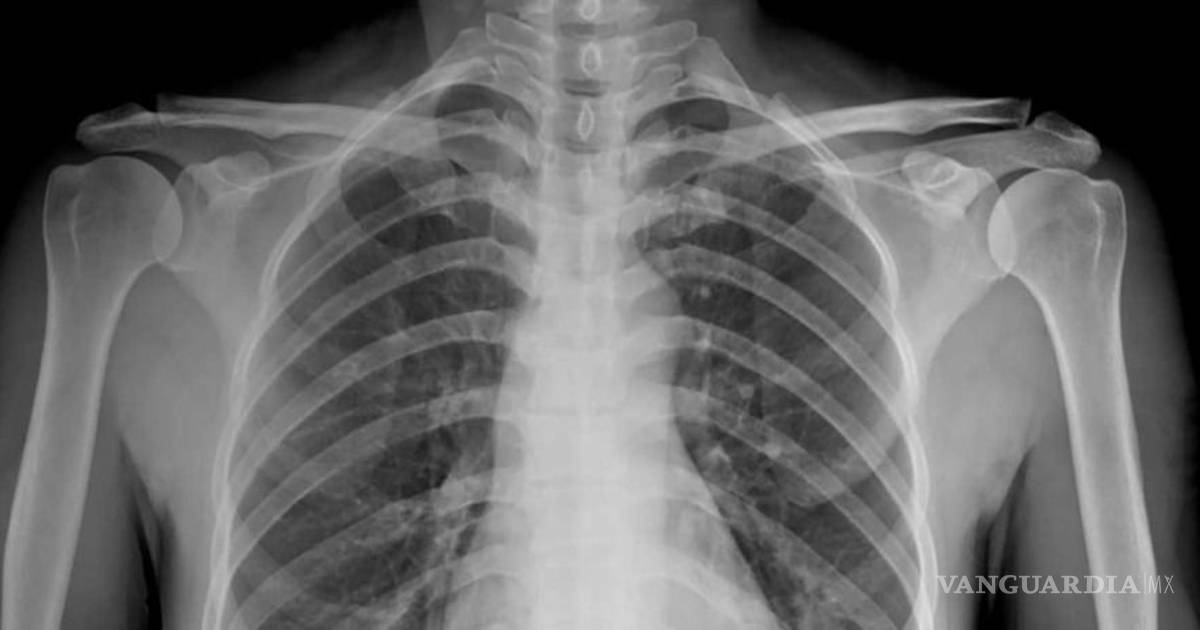

Los pulmones de un paciente sano deberían verse limpios y con mucho espacio negro, que es básicamente aire, mientras un pulmón de un fumador tiene líneas blancas, como una especie de neblina, que son indicativas de cicatrización y congestión.

Sin embargo, los pacientes post covid, muestran pulmones que parecen estar casi completamente blancos, en otras palabras, severamente dañados.